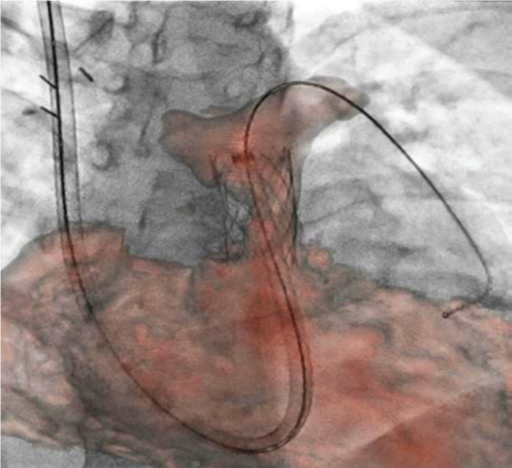

Завдяки маркерам співставляють МРТ об’єм зі скопічним зображенням.

Для точного співставлення використовують рентген зображення в прямій та боковій проекціях.

3D анатомія використовується як дорожня карта (так зв. Roadmap)

Накладений 3D об‘єм полегшує маніпуляцію катетером через складну анатомію пацієнта, допомогає точно розташувати стент і клапан легеневої артерії.